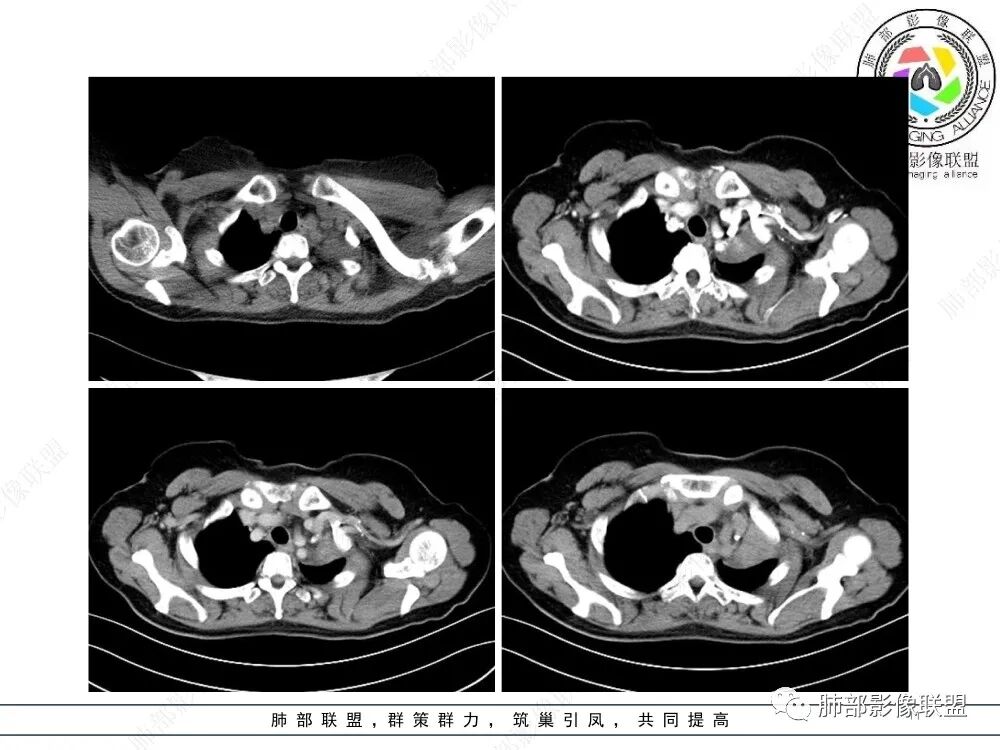

1、简要病史:老年女性,以受凉后咳嗽伴胸闷就诊,无咳痰、发热及其他不适,病程4月;既往体健。实验室检查中性粒细胞稍高,PCT稍高,CEA、细胞角蛋白19片段、鳞状细胞癌抗原正常。

2、影像表现:正常肺背景,左肺上叶支气管腔内占位,上叶支气管截断,远端肺组织不张,强化差异衬托出肺门区结节影或块状影。增强扫描腔内占位轻中度不均匀强化,可见坏死,远端粘液栓,局部肺动脉受压、侵犯,纵膈淋巴结无明显肿大,无胸腔积液。

就本例而言,患者为女性,无肺气肿背景,未提及吸烟史,影像上强化程度偏轻,未见湖泊样坏死,尽管中央型肺癌中以鳞癌最多见,且造成完全阻塞及肺不张,但在女性患者诊断鳞癌仍需谨慎。支气管腔内结节,强化程度轻,涎腺肿瘤需要考虑,不典型类癌也不能除外。女性患者,未提及吸烟史,尽管未见纵膈淋巴结明显肿大,但支气管明显相关,小细胞肺癌亦应当重点排除。